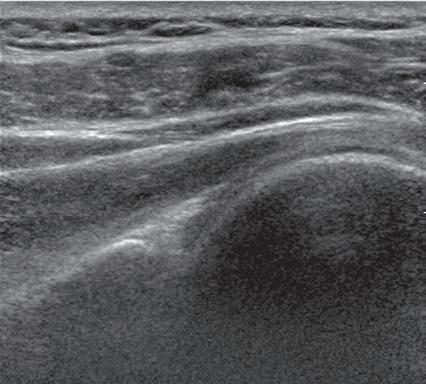

FIGURE 1.12 Anisotropy. Ultrasound images of tibialis posterior (P) and flexor digitorum longus (F) tendons in short axis at the ankle show normal tendon hyperechogenicity (A) and hypoechoic anisotropy (open arrows) (B), when angling or toggling the transducer along the long axis of the tendons, thus aiding in identification of tendons relative to surrounding hyperechoic fat.